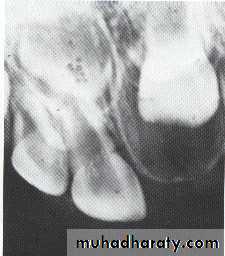

A: Odontogenic fibroma

B,C,D:Odontogenic myxoma.Odontogenic Adenomatoid Tumor (OAT)

The maxillary left canine and premolar have been displaced superiorly by the tumor.

The canine and lateral incisor have been displaced by the lesion.Soap bubble-like radiolucencies